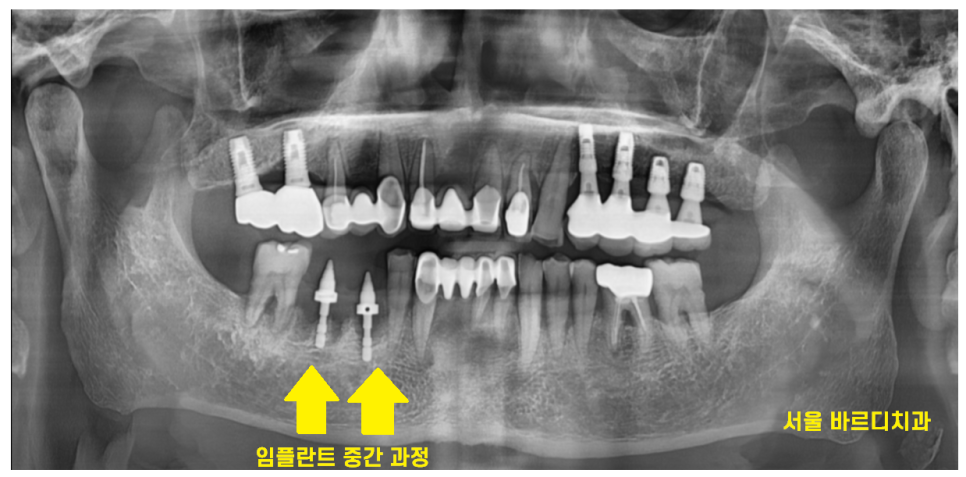

치아 욱신거림 일찍 오셨으면

2개의 치아도

치료해보면서 살려보았겠지만

시기를 놓쳐서 발치 후

하남시청치과에서 임플란트 수술을 진행하였습니다.

23.05.01

하남시청치과에서는 임플란트 후

기다리는 기간동안

다른 치아 잇몸치료를 진행해드렸습니다.

23.10.26